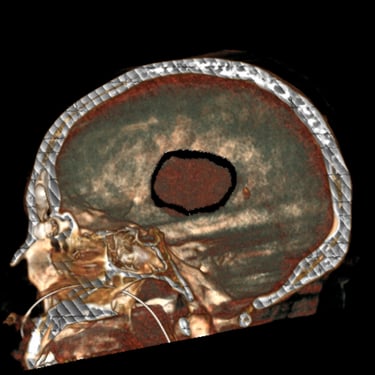

Hemorragia Intracerebral: Craneotomía y Evacuación del Hematoma

La hemorragia intracerebral es una emergencia neurológica grave que requiere diagnóstico rápido y tratamiento oportuno. Cuando el hematoma produce efecto de masa, deterioro del estado de conciencia o riesgo de herniación, la craneotomía y evacuación quirúrgica se convierten en la opción indicada. Este procedimiento permite abrir la bóveda craneal, retirar el coágulo y disminuir la presión intracraneal, preservando la función neurológica. Su objetivo es detener el daño secundario, mejorar la perfusión cerebral y estabilizar al paciente. La intervención temprana, combinada con cuidados críticos especializados, aumenta las posibilidades de supervivencia y recuperación funcional en este tipo de emergencia.